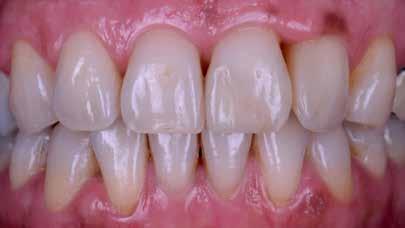

nak megfelelően – előkészítjük (orthofoszforsavval történő savazás, lemosás, szárítás és bond réteggel történő fedés). Ezzel egyidejűleg a ragasztásra kerülő héjak is előkészítésre kerülnek (hidrofolysavval történő savazás, lemosás, szárítás, szilanizálás, bond réteggel történő fedés, és végül az alkalmazni kívánt ragasztóanyag felvitele). Ezután a héjakat a fogak felszínén egyesével pozicionáljuk, majd néhány másodpercen keresztül polimerizációs lámpa segítségével megvilágítjuk. Ezt követően a kifolyó ragasztófelesleget eltávolítjuk, majd elvégezzük a restaurátumok végső polimerizálását. A héjak végleges rögzítését követően az esetlegesen visszamaradt ragasztómaradványok eltávolításra kerülnek, valamint ellenőrizzük az okklúzió és artikuláció közben létrejövő fogérintkezéseket. Az optimális esztétikai eredmény biztosítása érdekében kiemelt jelentősége van a papillák helyreállításának (rózsaszín esztétika). A modern fogorvoslás egyik kiemelt célja a fehér- és rózsaszín esztétika közti harmonikus egyensúly megteremtése. A papillák színe, nagysága és szimmetrikus megjelenése meghatározó szerepet tölt be a rózsaszín esztétika kialakításában. Az íny lefutása ugyancsak rendkívül jelentős mértékben befolyásolja a páciens fogazatának esztétikus megjelenését.

A cikkünkben bemutatásra kerülő eset ellátása során preparációt nem igénylő héjak készítése mellett döntöttünk. A héjak készre vitele során a platinafólia technikát alkalmaztuk. Annak ellenére, hogy az elkészítésre kerülő héjak rendkívül vékonyak, és ezáltal a végleges rögzítésük előtt jelentős törésveszéllyel állunk szemben, összességében mégis olyan minimál invazív kezelési eljárásnak számítanak, amely segítségével kifogástalan esztétikai eredményeket lehet elérni. A fent leírtak alapján bátran javasoljuk e módszer alkalmazását.